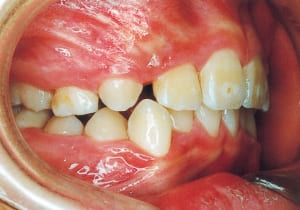

1 Initial Visit 2-11-’88

3 Initial Visit 2-11-’88

4 Initial Visit 2-11-’88

The Class II condition is pronounced, with a significant overjet of 12.5 mm(3). Although the teeth size are large, crowding is relatively mild. The maxillofacial structure has good depth and a robust bone framework(5). The mandible itself is solid , robust gonial angle, but there is significant anterior-posterior displacement relative to the maxilla(ANB 10.0°). While there is no confirmed history of thumb-sucking or similar habits, the lower lip is already pushing up against the maxillary incisors. The cause of this condition is unknown.